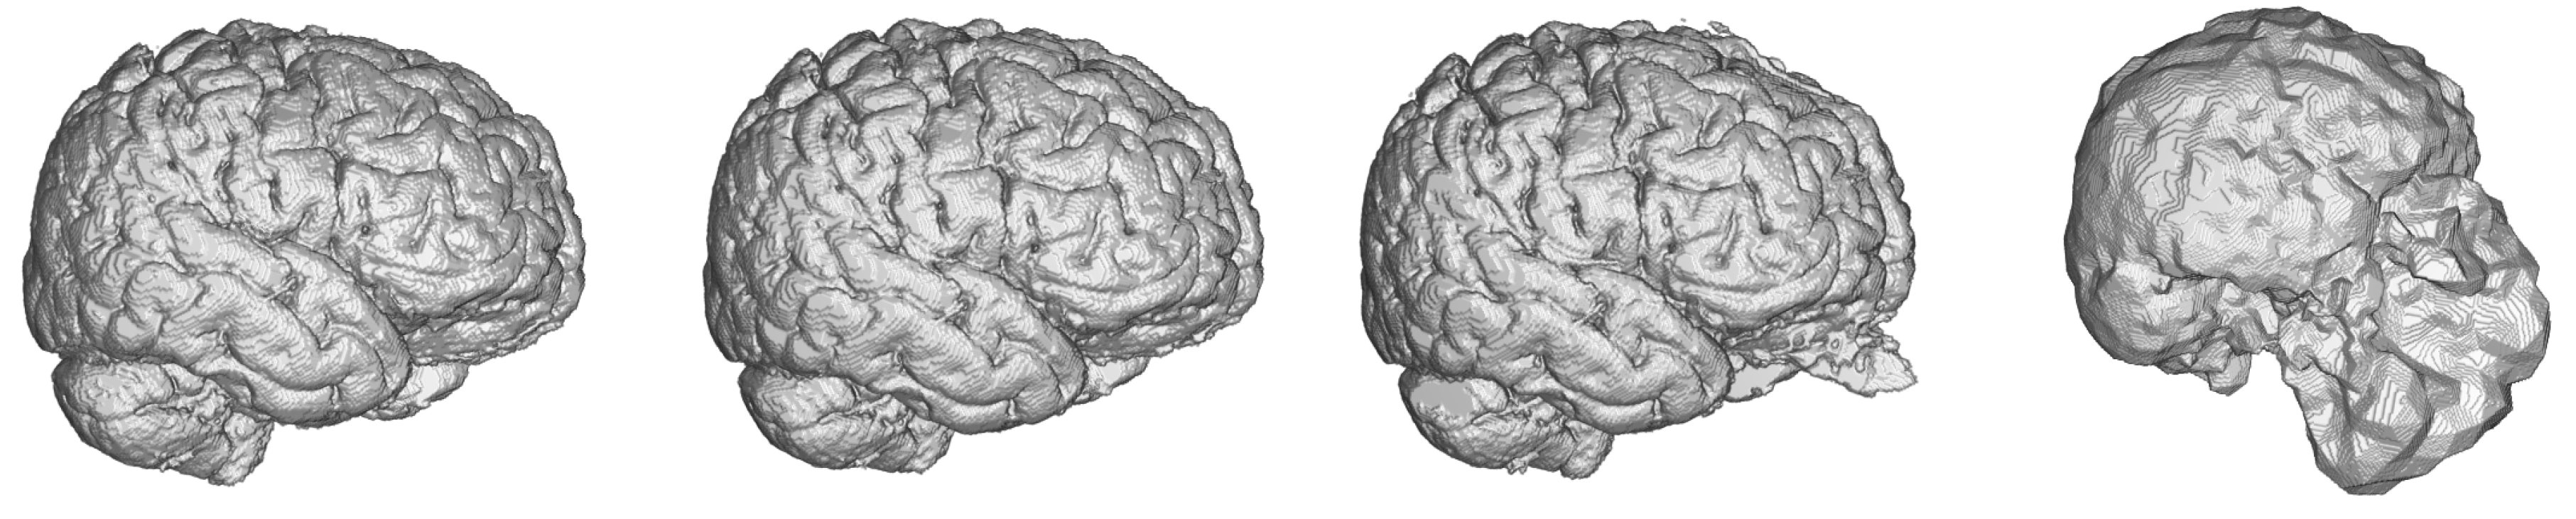

Dense-U-Net network proved to give the best performance in all considered metrics in 3D processing mode. There should be stated, that even segmentation using basic U-Net network gave better accuracy than a human expert. When compared to other 2D networks, the Dense-U-Net had better results in all metrics except for average Hausdorff distance. This is most probably caused by the fact that 50 epochs of training was not enough for a network with so many parameters and therefore the network generated more artifacts in the output segmentation than the simpler versions. As can be seen in Figure 7 the methods had problems segmenting the area around nasal cartilage. FSL method results in this case were unusable for medical praxis. Dense-U-Net network had the best results also thanks to the fact, that it was able to successfully segment this area on the MRI scan.

Figure 7.

Visualisation of predictions from 3D benchmark brain models and FSL segmentation. From left to right—Dense-U-Net, Residual-U-Net, U-Net, FSL.

After the evaluation in the benchmark phase we trained the 3D Dense-U-Net again, now with 99 epochs, to get the final fine-tuned model. Obtained results are in Table 5.

The Dense-U-Net network was trained in the fine-tuning phase (99 epochs) and validated using 3-folds cross-validation. In all five metrics the results are more accurate than a human expert. Output of the segmentation is visualised in Figure 8. It is clearly visible, that the proposed segmentation output overcame the human results and also results of older methods not based on deep neural networks such as the FSL. The network was able to learn the input image features as well as to generalize the brain segmentation problem. All the evaluations were made using data independent to training and the validation data.

Figure 8.

Comparison of ground truth brain model (left) and brain model segmented by Dense-U-Net (right) after the final phase of training.